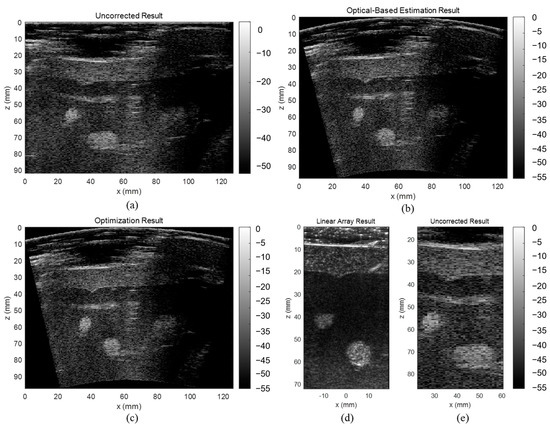

3.3. ABDFAN Phantom and Liver Scan Results

The uncorrected, optical-based estimation, and optimization results of the ABDFAN phantom and liver scan are shown in Figure 10 and Figure 11. The ground truth images from the linear array transducer are shown in Figure 10d and Figure 11d, and the same regions are cropped from the flexible array transducer results, and examples of the uncorrected results are depicted in Figure 10e and Figure 11e. The uncorrected results have significant distortions compared with the ground truth and corrected results. To quantitatively analyze the distortion, the cysts, blood vessels, and mussels are segmented as shown in Figure 12, and the Dice score, Jaccard index, and Hausdorff distance between the results and ground truth are evaluated and listed in Table 5, Table 6, and Table 7. The results show that both estimation and optimization algorithms can correct the distortions of the reconstructed image, and there is no significant difference between the two algorithms. The CNR and GCNR of the center cyst in the ABDFAN phantom and the large blood vessel in the liver scan are listed in Table 5, Table 6, and Table 7. In conclusion, the images reconstructed by both algorithms have an overall higher accuracy and contrast than the uncorrected images, and the optimization algorithm has a slightly better performance on estimating the array shape.

Figure 10.

Reconstructed images of the ABDFAN phantom (a) without array shape correction, (b) with optical-based estimated shape and (c) optimized shape, (d) ground truth image from the linear array transducer, and (e) cropped image with the same region as the ground truth.

Figure 11.

Reconstructed images of the liver scan (a) without array shape correction, (b) with optical-based estimated shape and (c) optimized shape, (d) ground truth image from the linear array transducer, and (e) cropped image with the same region as the ground truth.